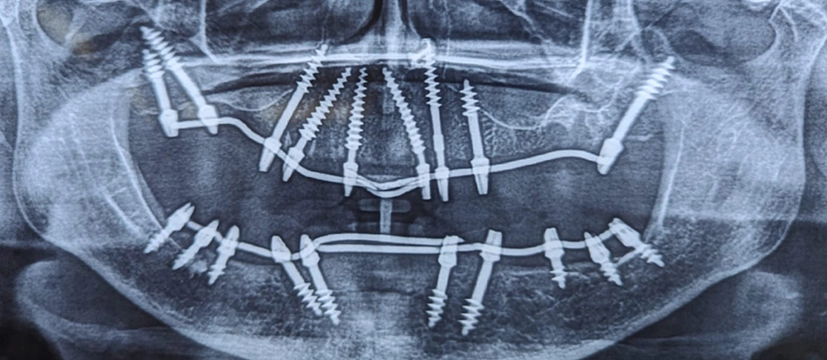

Basal implants are a type of dental implant used to replace missing teeth.

Unlike traditional implants, which rely on the jawbone for support, basal implants anchor into the cortical bone, providing stability even in cases of bone loss. This makes them suitable for patients with reduced bone volume or quality.

Basal implantology is an innovative approach to implant dentistry that focuses on utilizing the basal bone, which has excellent density and provides exceptional support for implants. Basal dental implants, also called cortical implants or bicortical implants, engage the cortical bone, ensuring stability and reducing the reliance on the compromised alveolar bone.

This technique has revolutionized the field of dental implantology by providing effective solutions even in challenging cases, such as patients with severe bone loss or inadequate alveolar bone. Basal dental implants utilize the strong basal bone, allowing for immediate function and reducing treatment time significantly.

- Implant placement: Titanium implants are inserted into the jawbone, providing a sturdy foundation for prosthetic teeth.